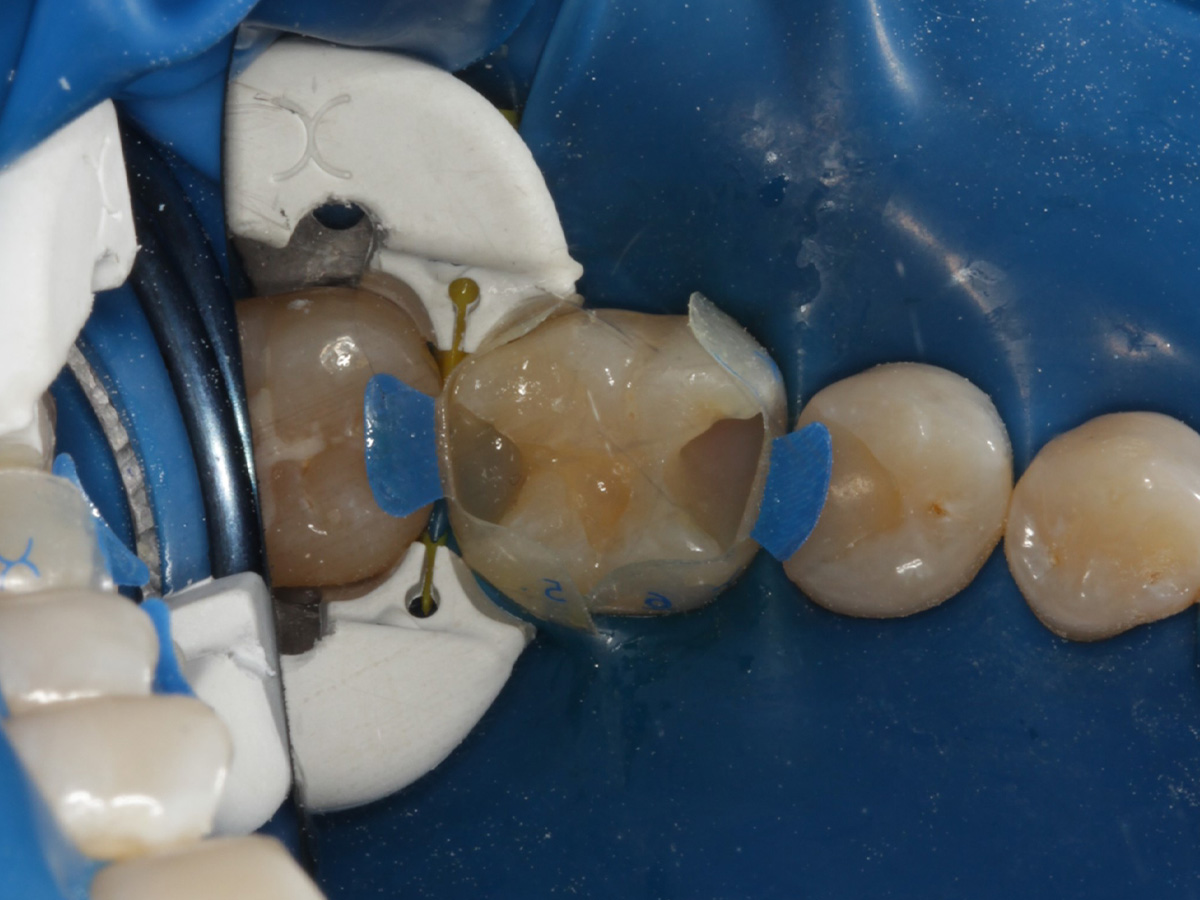

Abbildung 2

Quadrantenisolierung mit Kofferdam (x-heavy)

Abbildung 3

Schutz des Nachbarzahnes und des Kofferdams mit wiederverwandter Bioclear Biofit Matrize (gereinigt und sterilisiert); Separation zur Applikation der Matrize mit Heidemannspatel

Abbildung 4

Defektdarstellung; „Schutzmatrizen“ ideal als „Leitplanken“ bei der Zahnpräparation tief approximal bis in gesunde Zahnsubstanz